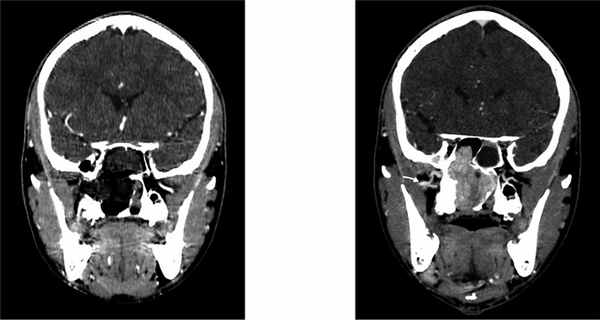

Подросток, 14 лет, обратился в клинику с жалобами на длительную двустороннюю заложенность носа и систематические носовые кровотечения. Возникновение симптомов впервые отметил 12 мес назад, обращался к врачу-оториноларингологу по месту жительства, получал лечение по поводу хронического риносинусита, без положительной динамики. При обращении в ФГБУ «НМИЦ ДГОИ им. Дмитрия Рогачева» была выполнена эндоскопия носа с визуализацией новообразования, обтурирующего полость носа и хоану справа. При выполнении МСКТ околоносовых пазух выявлено сосудистое новообразование полости носа, носоглотки и околоносовых пазух с патогномоничными рентгенологическими признаками ЮАН. В соответствии с классификацией Fisch-Andrews данная ЮАН стадирована как IIIa: опухоль заполняет клиновидную пазуху, носоглотку, распространяется в крыловидно-небную ямку, далее через нижнюю глазничную щель в полость орбиты; опухоль разрушает большое крыло клиновидной кости и крыловидный отросток, распространяясь в закрыловидное пространство. МСКТ околоносовых пазух также позволила визуализировать правую ВВА, которая проходила непосредственно за задней стенкой верхнечелюстной пазухи (см. рисунок). Данное положение ВВА позволяет выполнить ее трансназальное клипирование. Учитывая этот факт, нами было принято решение удалить ЮАН без предварительной эмболизации. Операция проводилась под общей анестезией, в условиях управляемой гипотонии. С целью хирургического доступа была выполнена модифицированная эндоскопическая медиальная максиллэктомия по Денкеру и этмоидотомия справа. Трансназальный модифицированный эндоскопический доступ по Денкеру включает в себя удаление медиальной стенки верхнечелюстной пазухи и расширение грушевидной апертуры латерально, что позволяет получить широкий хирургический коридор, достаточный для манипуляций в области подвисочной ямки [10]. Для обеспечения адекватной широты хирургического пространства и мобилизации опухоли была произведена двусторонняя сфенотомия с резекцией рострума и перегородки клиновидной пазухи. Затем задняя стенка верхнечелюстной пазухи была резецирована, выполнена экспозиция содержимого подвисочной ямки путем рассечения ее периоста серповидным скальпелем. После бережного выделения ВВА было выполнено, используя клипаппликатор, наложение двух титановых клипс на ее основной ствол. Далее компонент опухоли в крыловидно-небной ямке был отсепарован от здоровых тканей, мобилизован компонент из полости орбиты. Дальнейшая диссекция опухоли, в частности резекция крыловидного отростка, вызвала кровотечение за счет дополнительного кровоснабжения опухоли из бассейна внутренней сонной артерии через видиеву артерию. Кровотечение остановлено биполярной коагуляцией. Несмотря на выполненные методы контроля гемостаза, во время операции отмечалось умеренное кровотечение, не затрудняющее удаление опухоли. После мобилизации всех компонентов опухоли ЮАН была низведена в ротоглотку и удалена трансорально. Послеоперационная полость заполнена пеной на основе карбометилцеллюлозы. Операционная кровопотеря составила 1100 мл и не потребовала гемотрансфузий. На следующие сутки после хирургического вмешательства пациенту была выполнена МСКТ с внутривенным контрастированием, которая не выявила признаков резидуальной опухолевой ткани. Стандарты лечения ЮАН в нашем отделении предполагают выполнение контрольной МСКТ с внутривенным контрастированием на 1—2-е сутки после операции для определения радикальности проведенной операции; в случае если по данным МСКТ визуализируется резидуальная опухолевая ткань, пациенту выполняется ревизионная операция с удалением остаточного компонента.

Рис.. МСКТ головы с контрастным усилением до и на вторые сутки после операции.